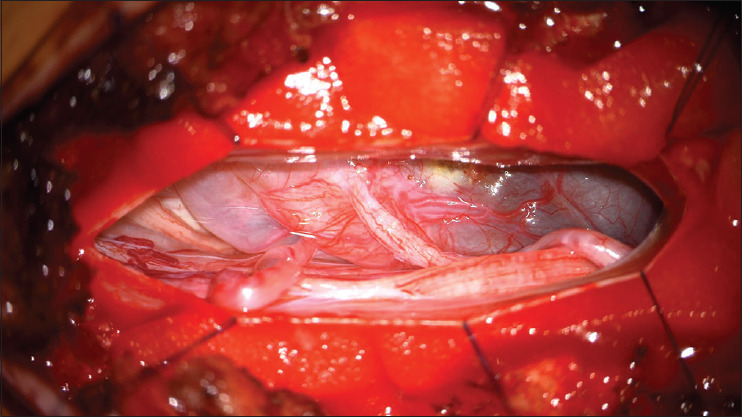

移动神经鞘瘤或雪旺细胞瘤是罕见的,但其在椎管内迁移的能力使诊断和治疗复杂化。我们报告两例下胸椎和腰椎的移动神经鞘瘤,均表现为间歇性腰痛和腿部疼痛以及腿部麻木。核磁共振成像显示囊性肿块随着时间的推移而改变位置,最终引起破坏性疼痛,促使手术干预。术后结果良好,突出了在术前计划中考虑肿瘤移动性的重要性。移动神经鞘瘤目前的诊断和手术挑战。认识到肿瘤移动的潜力对于制定有效的治疗策略至关重要,因为它影响临床表现和手术方法。

Mobile schwannomas, or schwann cell tumors, are rare, but their ability to migrate within the spinal canal complicates diagnosis and treatment. We report two cases of mobile schwannomas in the lower thoracic and lumbar spine, both presenting with intermittent low back and leg pain and leg numbness. MRIs revealed cystic masses that shifted positions over time, eventually causing disruptive pain that prompted surgical intervention. Postoperative outcomes were favorable, highlighting the importance of considering tumor mobility in preoperative planning. Mobile schwannomas present diagnostic and surgical challenges. Recognizing the potential for tumor mobility is crucial in developing effective treatment strategies, as it impacts clinical presentation and surgical approach.